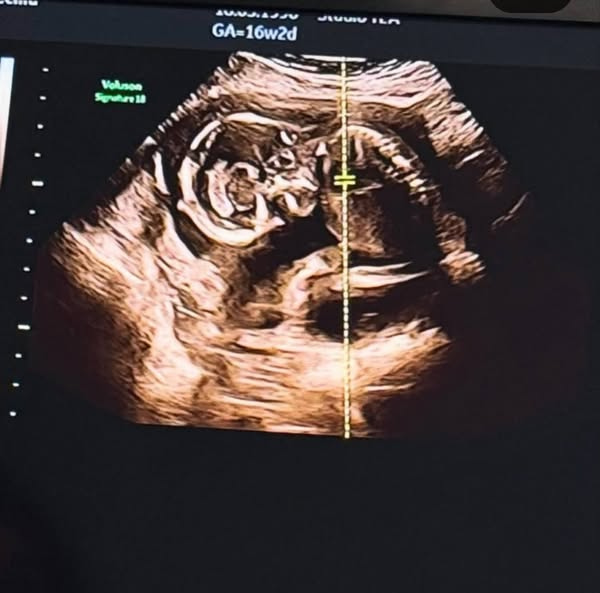

Ecco riportate, di seguito, le parole di Cecilia sul suo profilo Instagram ufficiale: “Ciao topolina, come tutte le cose straordinarie ti sei fatta desiderare molto ma ora eccoci qua a sentire il tuo cuoricino battere. Vedere quel bel nasino che spesso copri con le tue manine, come a non volerci rovinare la sorpresa di quando arriverai tra noi…La tua mamma e il tuo papà non vedono l’ora di conoscerti, abbracciarti, amarti e vederti crescere… a presto piccola Clara Isabel”.